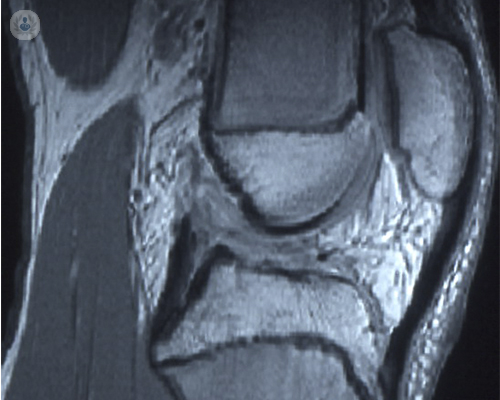

La rodilla es la articulación más afectada por la artrosis

La artrosis es una enfermedad degenerativa que afecta a las articulaciones, sobre todo afectando al desgaste de la rodilla. El Dr. Strauch, experto en Traumatología, habla de la patología y de su tratamiento.